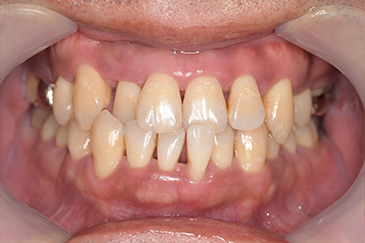

CASE 4

Before

After

基本情報

| 年齢・性別 | 52歳・女性 |

| 主訴 | クリーニングしたい |

| 治療内容 | スケーリング・PMTC |

| 治療期間 | 60分 |

| 治療費 | 約7,000円 |

| リスク・副作用 | 知覚過敏、歯肉退縮 |

| 治療方針 | 歯石とステインを除去して、今後は定期検診でのクリーニングと併せてガムピーリングやホワイトニングを行います。 |

| 担当者所見 | 歯肉の色素沈着が目立つため、ガムピーリングを行いながらホワイトニングを行うことをおすすめします。 |